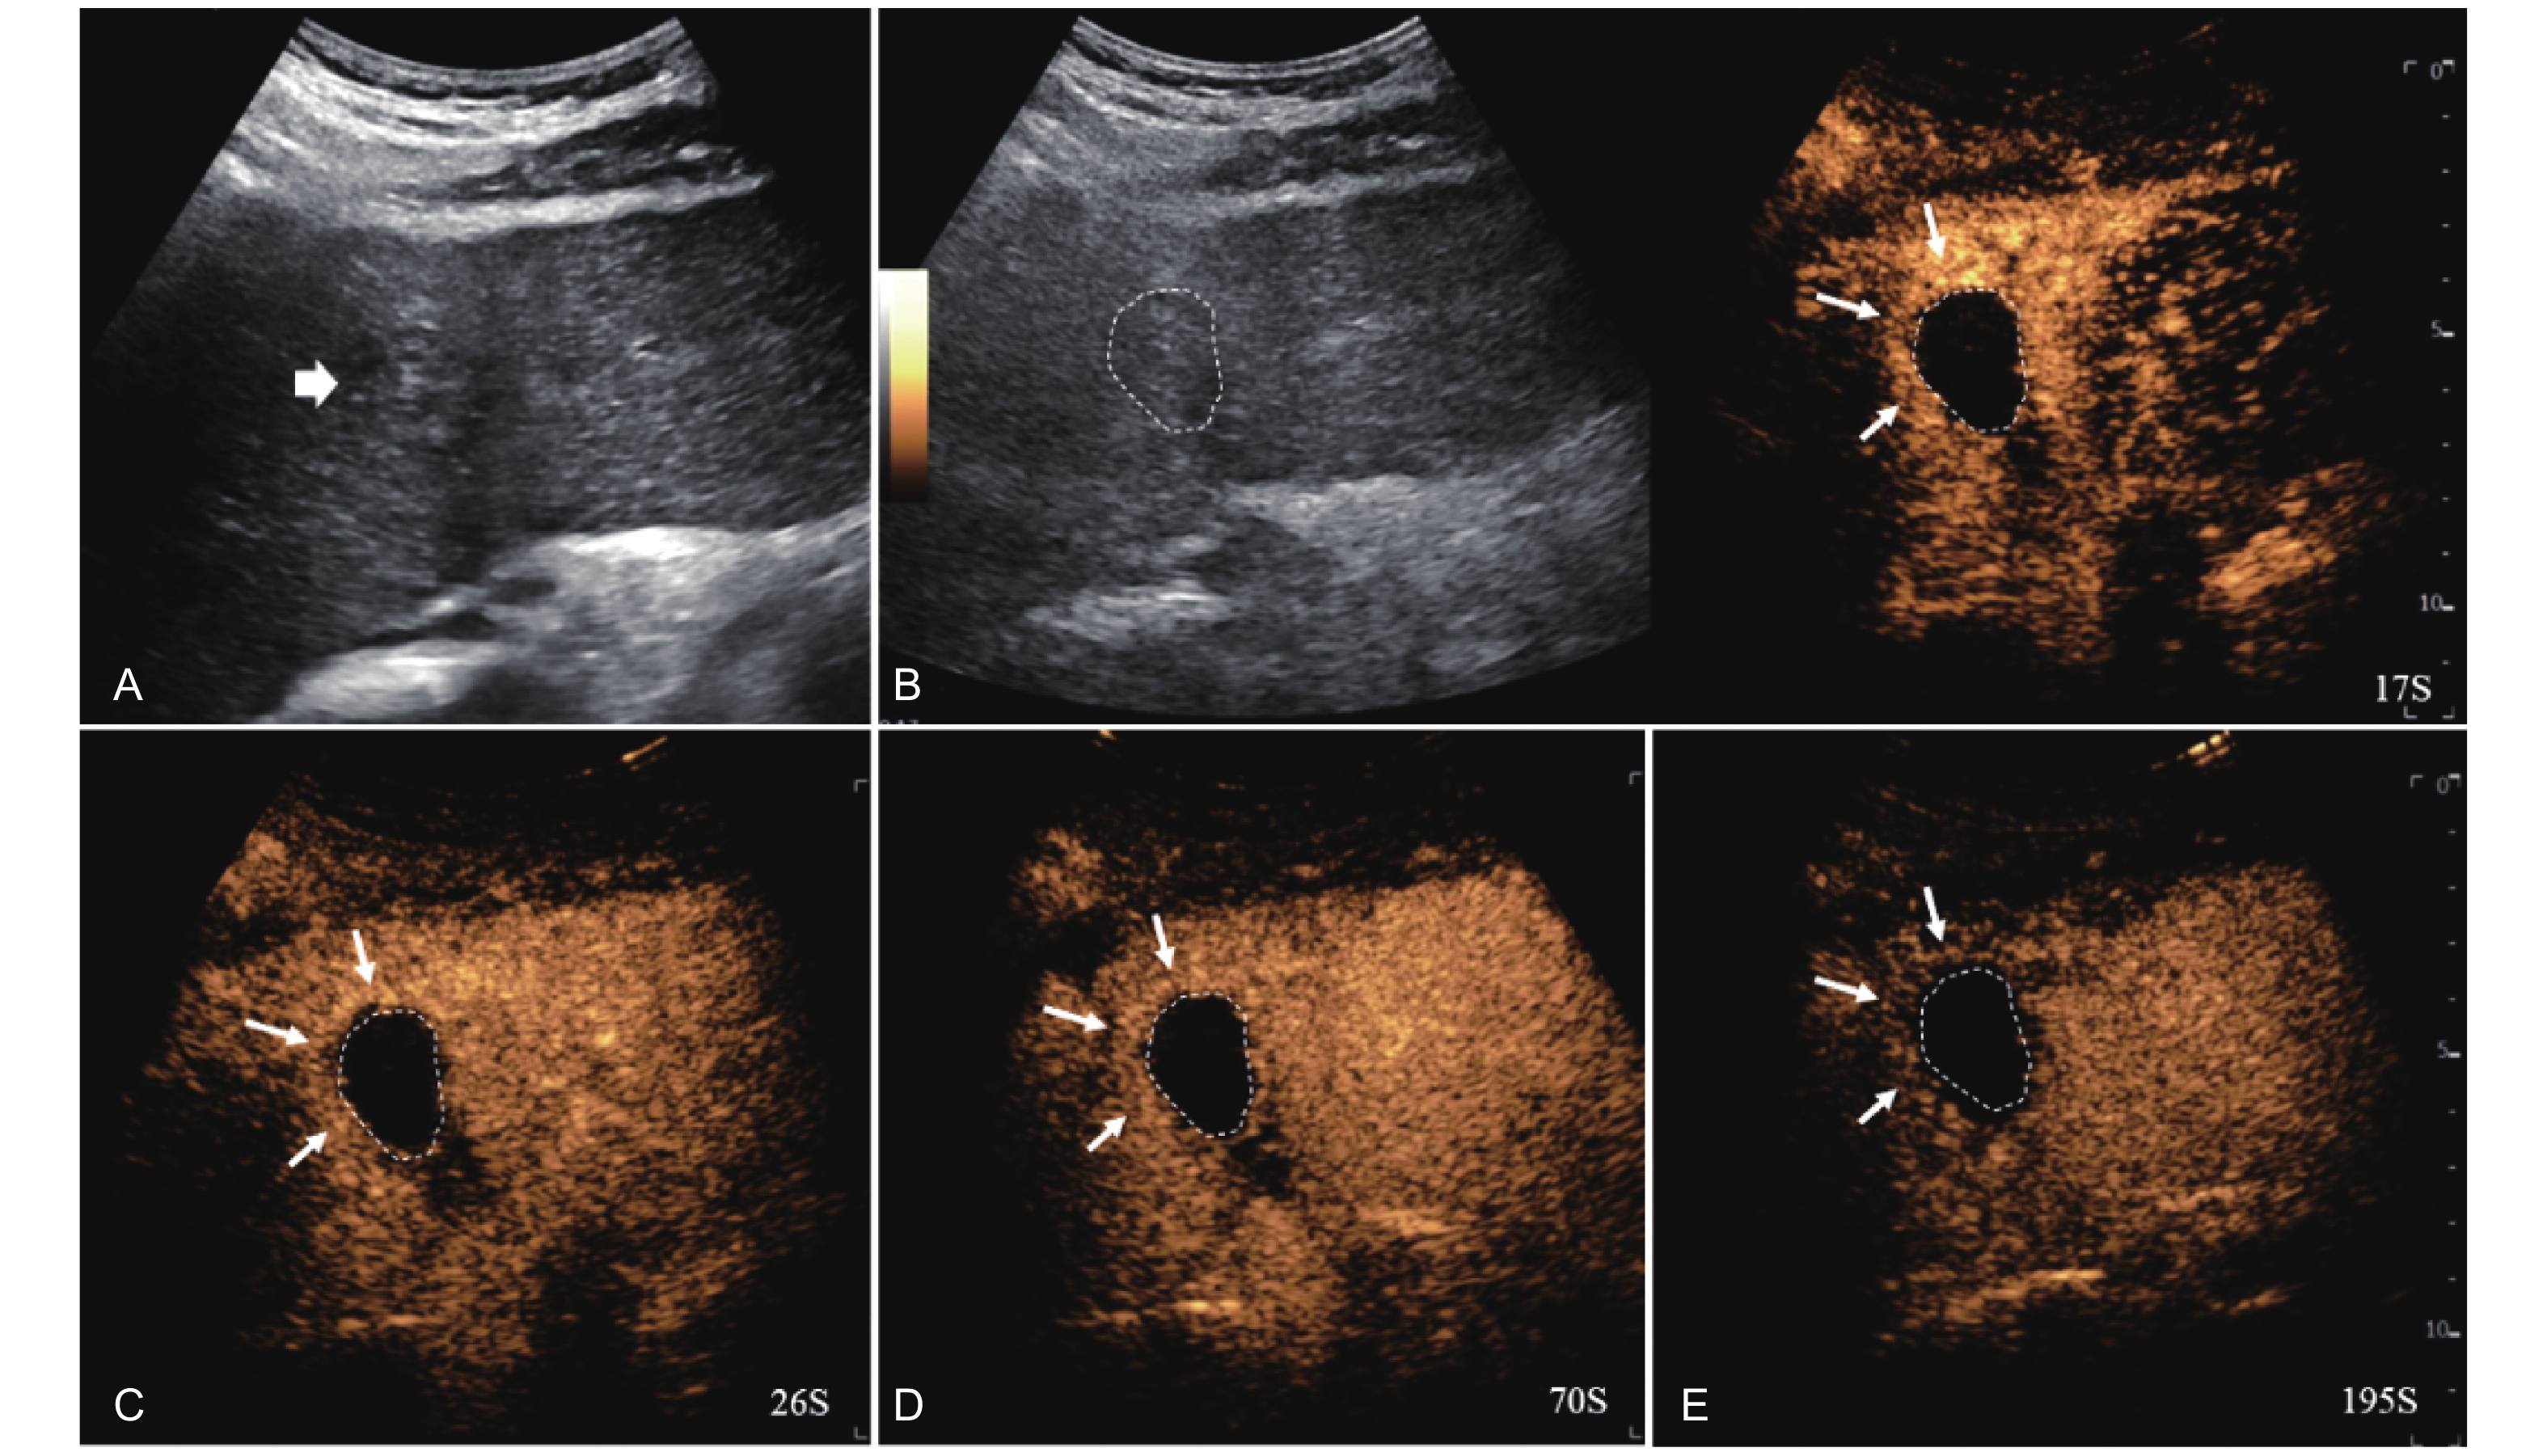

Figure 4

LR-TR Nonviable. Example of a nonviable tumor 14 days after TACE. (A) B-mode image shows two heterogeneous hyperechoic lesions (thick arrow) with irregular shape, measuring 17 mm and 18 mm in segment VI; (B-E) CEUS shows no intralesional enhancement with perilesional enhancement identical to the surrounding liver parenchyma in all phases. Findings are consistent with LR-TR Nonviable."